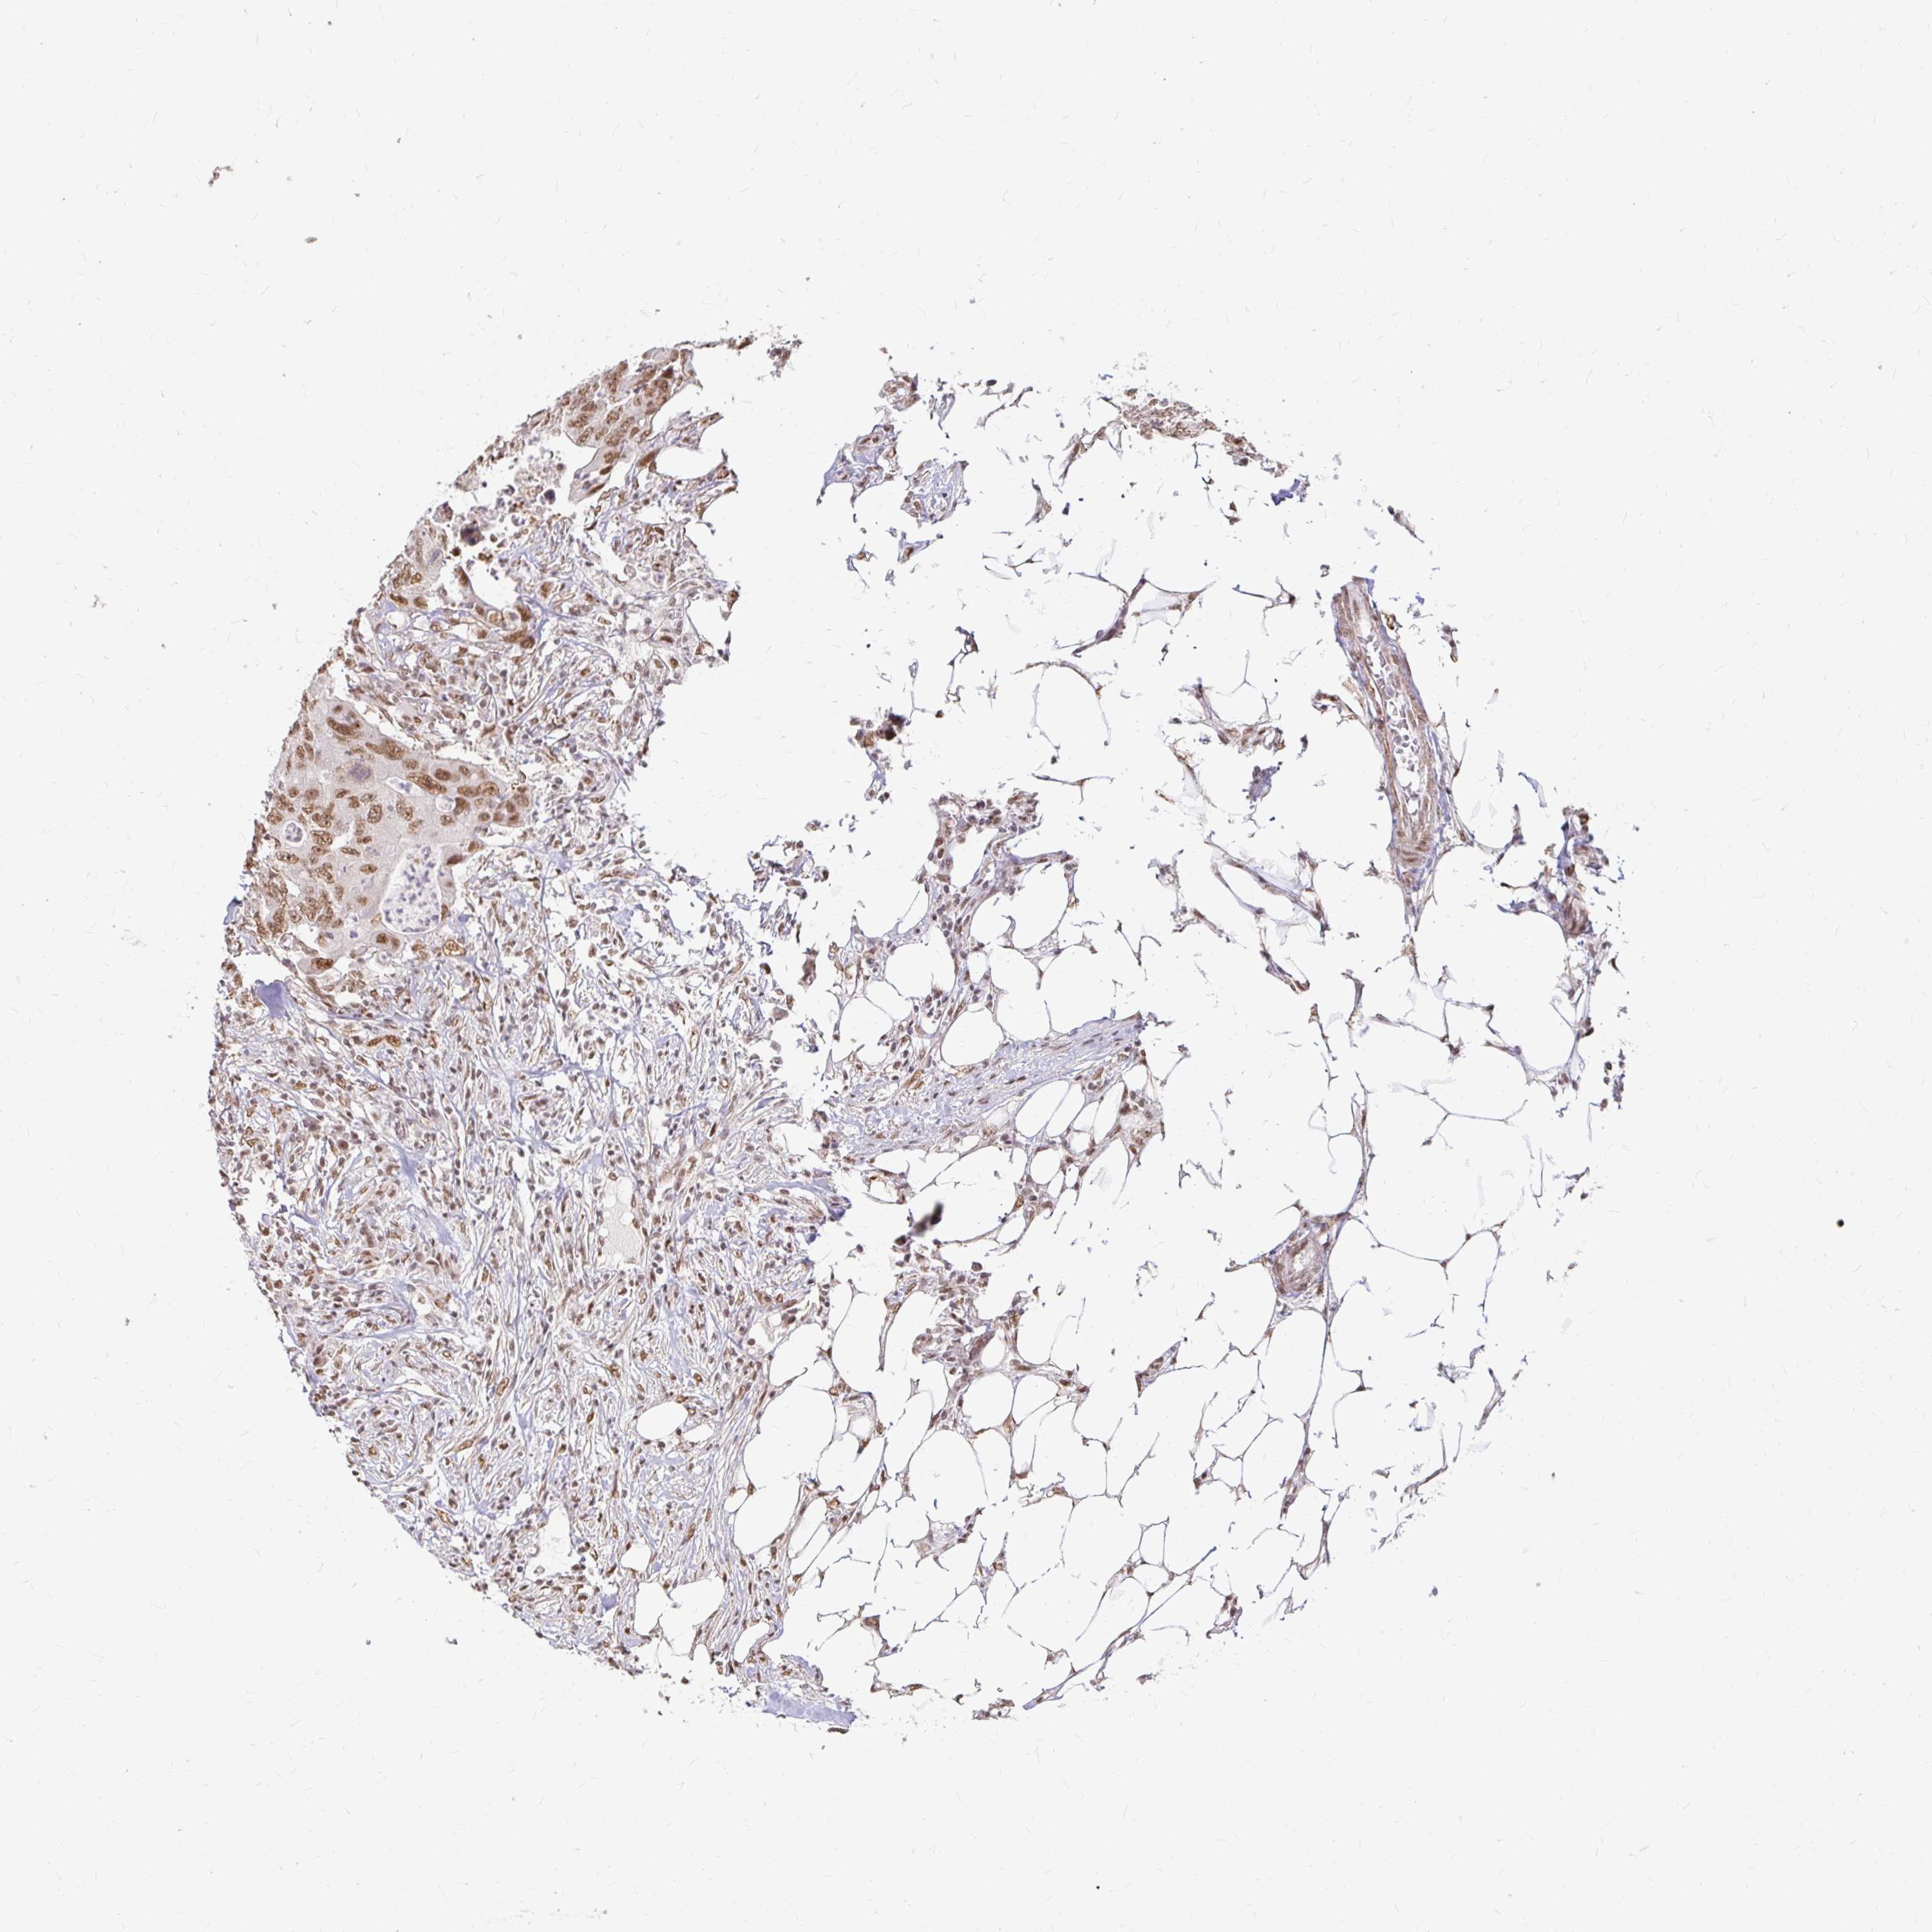

Colorectal cancer

Colon adenocarcinoma

Rectum adenocarcinoma